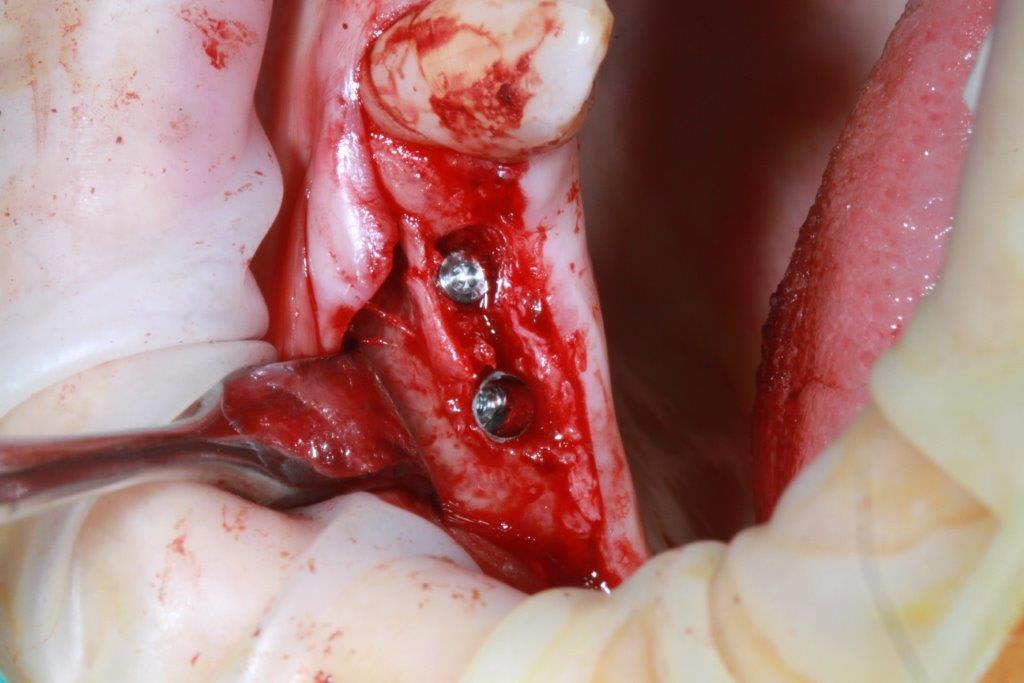

regarde moi ça pxav c'est la suite de mon cas

-> crete de 2 mm , expansion pour mettre du 3.7 sur 13 et 15 + summers dans la même séance sur 15

-> et regarde voir 6 mois après on voit que la 15 s'est légèrement enfoncée sur 2 mm :))))) expansion + summers ça faisait peut être beaucoup.

-> je lui ai posé les vis

-> Et je vais devoir exceptionnellement faire dès pilier CFAO pour corriger très légèrement l'axe (Implants légèrement vestibulés)

Photo 1 expansion plus summers

Photo 2-3 : 6 mois après